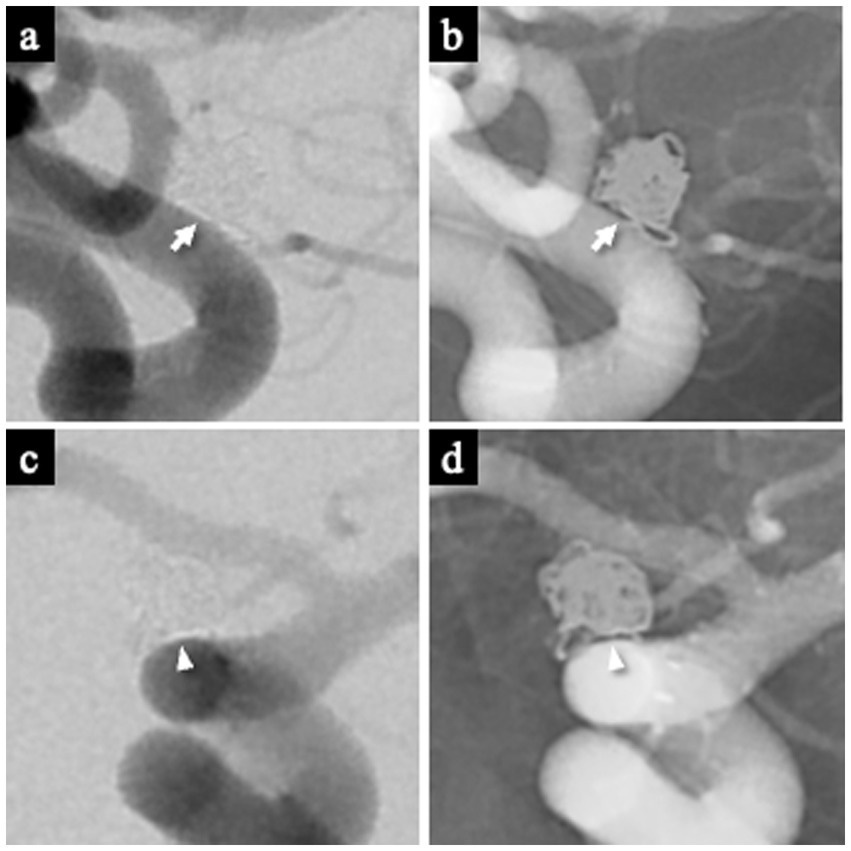

Assessment of the white-collar sign

The WCS was assessed on 1-year follow-up DSA. It was defined as a contrast-void, slit-like region extending across the aneurysm neck between the coil mass and the parent artery, visible on both subtracted and non-subtracted images (11). The optimal projection demonstrating the neck interface between the sac and parent artery was used for primary evaluation (Figures 3a,b), and this was supplemented by a down-the-barrel view when necessary (Figures 3c,d). Cases showing only partial non-filling zones were categorized as WCS-negative (12).

Figure 3

Representative images demonstrating the white-collar sign (WCS). (a,b) Left ICA aneurysm 1 year after coil embolization, showing a distinct interface between the aneurysm sac and the parent artery lumen. The WCS appears as a radiolucent gap (white arrow) on both DSA (a) and the corresponding nonsubtracted image (b). (c,d) Left ICA aneurysm 1 year after coil embolization visualized on the down-the-barrel view. The WCS (white arrowhead) is identifiable on both DSA (c) and the corresponding nonsubtracted image (d). WCS, White-Collar Sign.